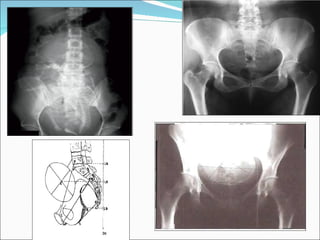

Radiopelvimetría Examen Complementario, a la pelvimetría obstetrica, que busca conocer la forma y diámetros pélvicos asistidos por la radiología. Tiene poca repercusión en la madre y el feto. A pesar de esto debe limitarse su uso, ya que no es necesaria ni útil para tomar decisiones desde el punto de vista obstétrico

Método de Thoms Es el método más usado para la radiopelvimetría. Cliché Anteroposterior: la embarazada sentada en la mesa de rayos X, y su espalda forma un ángulo de 45° con la horizontal    forma del estrecho superior y sus diámetros. Cliché de Perfil: la mujer de pie, en este cliché se obtiene el conjugado obstétrico, la forma del sacro y su longitud. Ademas si la cabeza fetal esta insinuada, podemos valorar la radioproporcionalidad

Radiopelvimetría Examen Complementario,a la pelvimetría obstetrica, que busca conocer la forma y diámetros pélvicos asistidos por la radiología. Tiene poca repercusión en la madre y el feto. A pesar de esto debe limitarse su uso, ya que no es necesaria ni útil para tomar decisiones desde el punto de vista obstétrico

Método de ThomsEs el método más usado para la radiopelvimetría. Cliché Anteroposterior: la embarazada sentada en la mesa de rayos X, y su espalda forma un ángulo de 45° con la horizontal  forma del estrecho superior y sus diámetros. Cliché de Perfil: la mujer de pie, en este cliché se obtiene el conjugado obstétrico, la forma del sacro y su longitud. Ademas si la cabeza fetal esta insinuada, podemos valorar la radioproporcionalidad